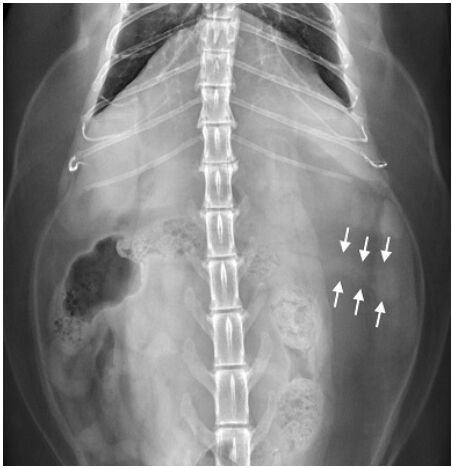

35.13歲,已絕育混種公貓,因嘔吐下痢就診,下圖為其腹腔X光影像,箭號所指為何?

(A)胰臟(pancreas)(B)脾臟(spleen)(C)小腸(small intestine)(D)淋巴結(lymph node)